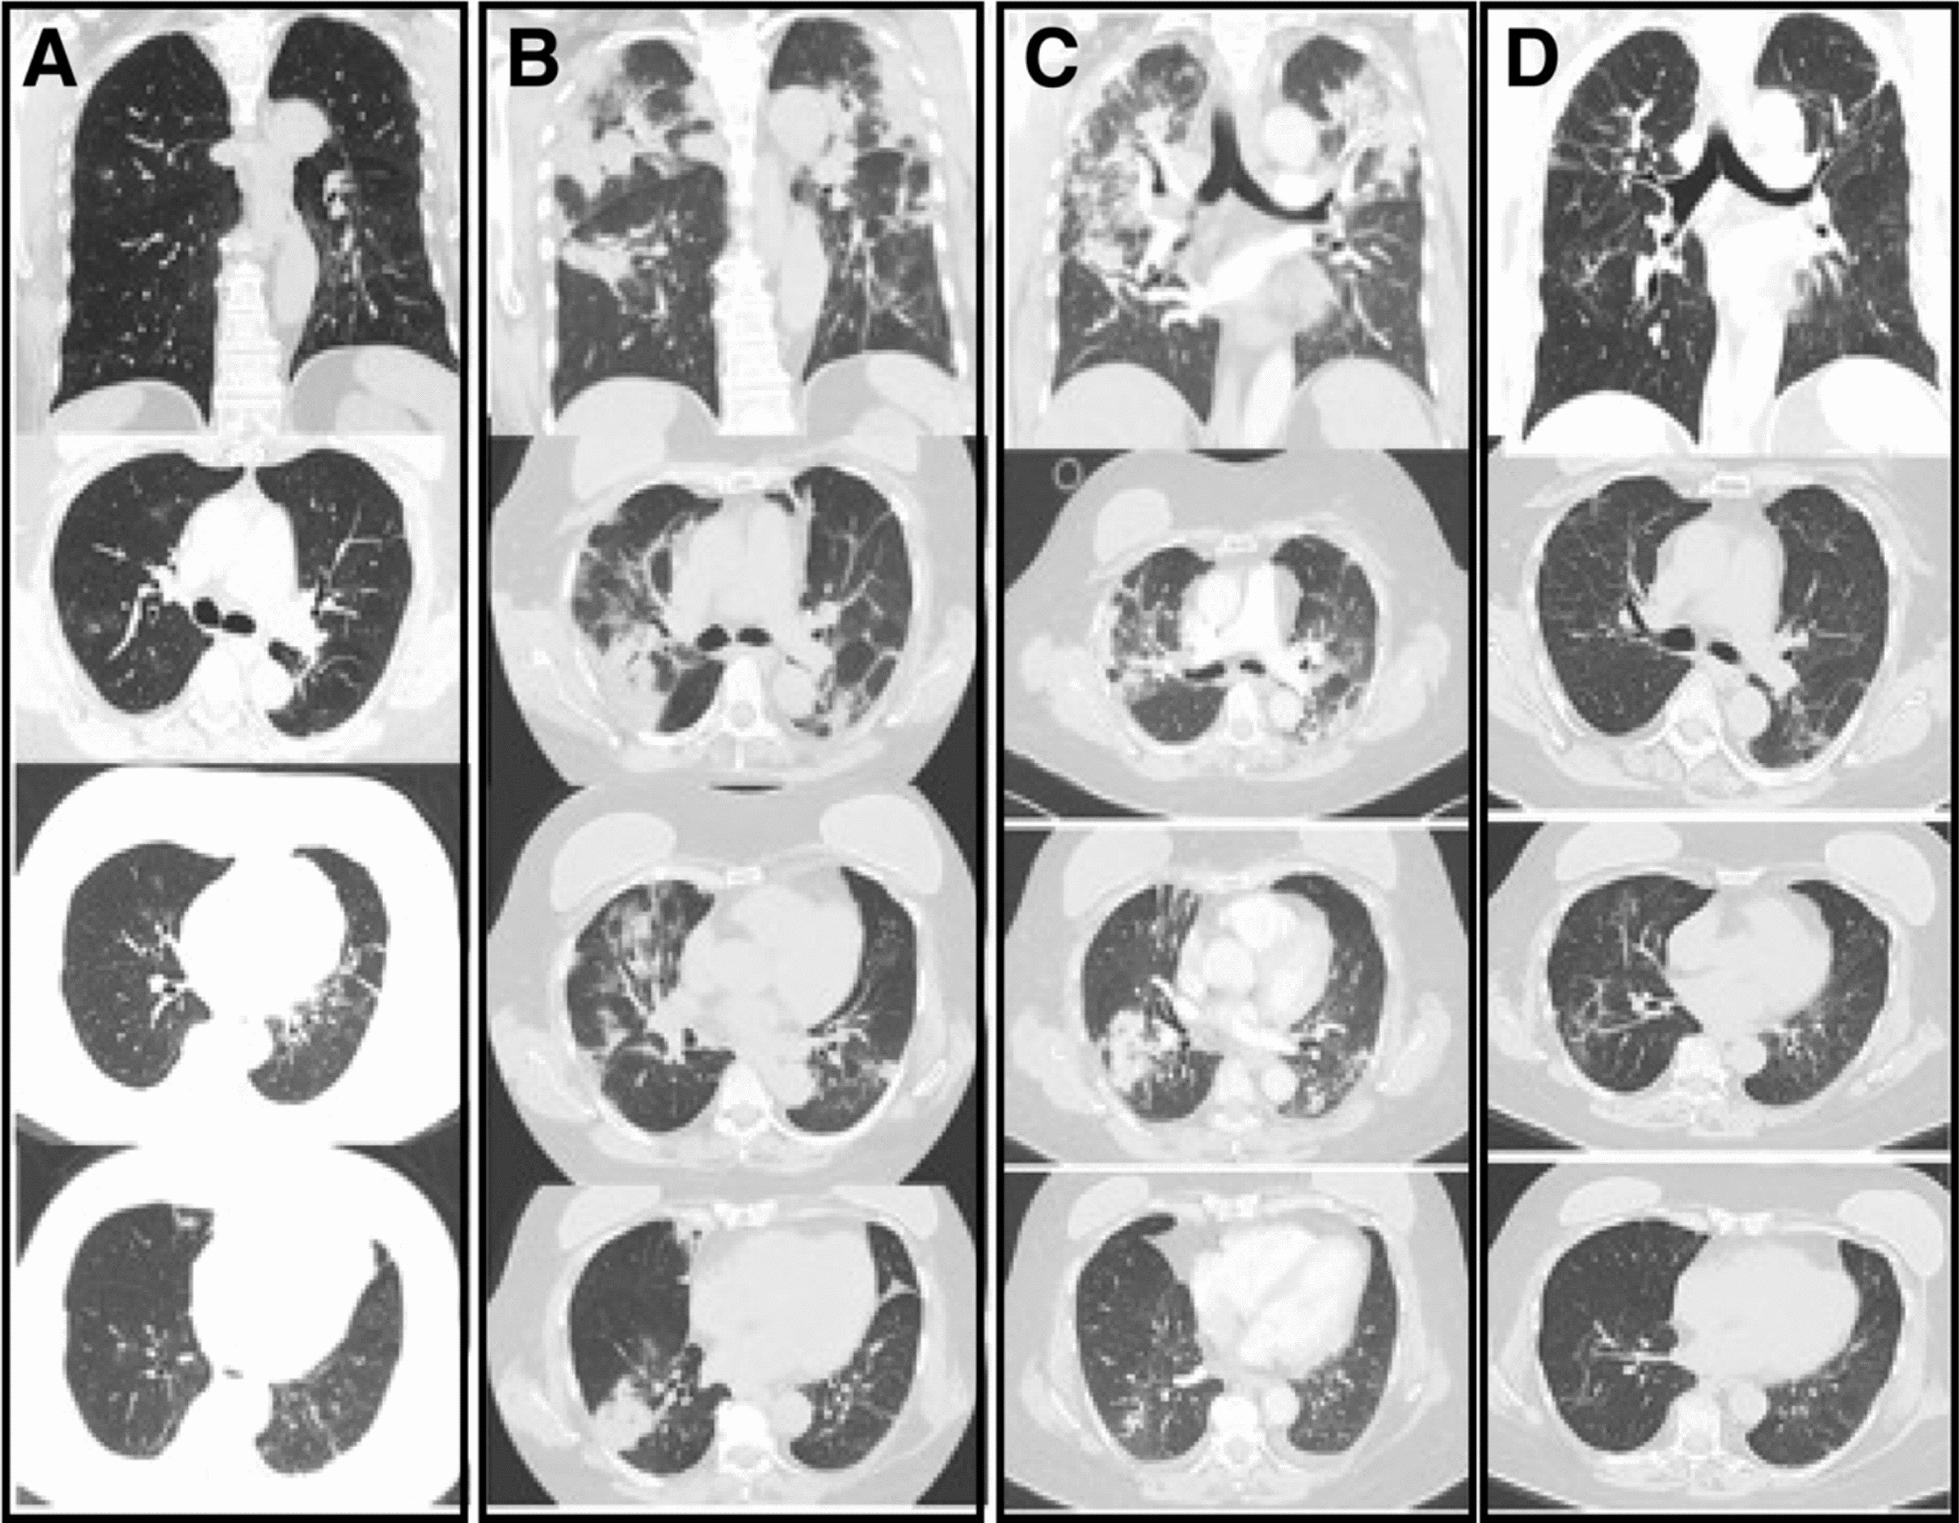

We report three cases involving mixed-race Colombian female patients aged 58, 35, and 63 years who experienced multiple episodes of coronavirus disease 2019 infection, with the most recent episode progressing to critical illness. These cases were characterized by relapses or persistent infections, and genomic analyses consistently identified the Omicron severe acute respiratory syndrome coronavirus 2 lineage as the causative variant. Notably, individuals with underlying immunosuppressive conditions developed severe acute respiratory syndrome coronavirus 2 infections that were more severe, leading to fatal outcomes that included acute respiratory distress syndrome, multiorgan dysfunction, and death. In contrast, one vaccinated patient with significant comorbidities exhibited persistent critical coronavirus disease 2019 but responded positively to treatment with tocilizumab.

我们报告了三例涉及不同种族的哥伦比亚女性患者的病例,年龄分别为58岁、35岁和63岁,她们经历了多次2019年冠状病毒病感染,最近一次感染进展为危重症。这些病例的特征是复发或持续感染,基因组分析一致确定奥密克戎严重急性呼吸综合征冠状病毒2谱系为致病变体。值得注意的是,患有潜在免疫抑制疾病的个体发生的严重急性呼吸综合征冠状病毒2感染更为严重,导致包括急性呼吸窘迫综合征、多器官功能障碍和死亡在内的致命后果。相比之下,一名患有严重合并症的接种疫苗患者表现出持续的2019年冠状病毒病危重症,但对托珠单抗治疗反应良好。